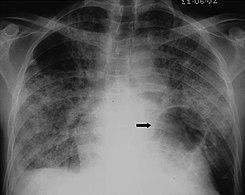

The diagnosis can be confirmed by the characteristic appearance of the chest X-ray and an arterial oxygen level (PaO2) that is strikingly lower than would be expected from symptoms. Gallium 67 scans are also useful in the diagnosis. They are abnormal in about 90% of cases and are often positive before the chest X-ray becomes abnormal. Chest X-ray typically shows widespread pulmonary infiltrates. CT scan may show pulmonary cysts (not to be confused with the cyst-forms of the pathogen).

X-ray of a cyst in pneumocystis pneumonia[6]